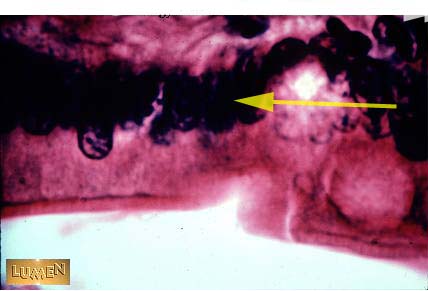

What kind of epithelium is this?

Simple Columnar